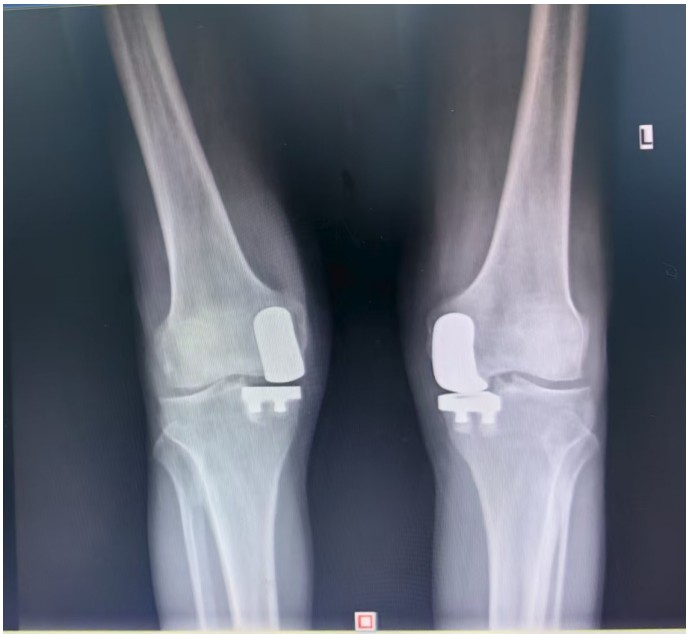

據(jù)了解,患者1年前無明顯誘因出現(xiàn)雙膝關(guān)節(jié)疼痛,以右側(cè)膝關(guān)節(jié)為主,近5個(gè)月來雙膝關(guān)節(jié)疼痛明顯加重,不但日常行走困難,生活質(zhì)量更是受到極大影響。經(jīng)多家醫(yī)院治療效果均不理想,了解到衡陽市中心醫(yī)院關(guān)節(jié)外科在關(guān)節(jié)置換領(lǐng)域擁有豐富的臨床經(jīng)驗(yàn)和良好的患者口碑,毅然決定赴衡求醫(yī)。醫(yī)生發(fā)現(xiàn)患者雙膝關(guān)節(jié)已有內(nèi)翻畸形,關(guān)節(jié)內(nèi)側(cè)骨性膨大,X線提示雙膝退行性病變,雙膝內(nèi)側(cè)間隙明顯狹窄,手術(shù)為最佳治療方式。為了達(dá)到根治目的,羅湘平主任醫(yī)師、彭健副主任醫(yī)師為患者進(jìn)行了詳細(xì)查體及綜合評(píng)估,術(shù)前組織開展多學(xué)科討論(MDT)。考慮到易叔叔的膝關(guān)節(jié)骨關(guān)節(jié)炎僅局限于內(nèi)側(cè),外側(cè)間室軟骨良好,若采用全膝關(guān)節(jié)置換術(shù)會(huì)將失去正常關(guān)節(jié)間室的軟骨與韌帶,創(chuàng)傷較大,便為其制定了右膝關(guān)節(jié)單髁置換手術(shù)治療方案。在充分完善術(shù)前準(zhǔn)備后,羅湘平主任、彭健副主任醫(yī)師團(tuán)隊(duì)為患者實(shí)施了右側(cè)膝關(guān)節(jié)單髁置換術(shù)。手術(shù)過程順利,團(tuán)隊(duì)?wèi)?yīng)用微創(chuàng)術(shù)式(MIS)及“精準(zhǔn)間隙平衡技術(shù)”,最大程度減少了手術(shù)創(chuàng)傷,為術(shù)后快速康復(fù)奠定了堅(jiān)實(shí)基礎(chǔ),術(shù)后第二天即可借助助行器下地活動(dòng)。6天后團(tuán)隊(duì)順利為患者實(shí)施了左側(cè)膝關(guān)節(jié)單髁置換手術(shù)。目前,易叔叔在關(guān)節(jié)外科醫(yī)護(hù)團(tuán)隊(duì)的精心指導(dǎo)和康復(fù)治療下,恢復(fù)情況良好,雙側(cè)膝關(guān)節(jié)活動(dòng)度輕松達(dá)到90°,膝關(guān)節(jié)功能顯著改善,能夠獨(dú)立下地行走,對(duì)手術(shù)效果非常滿意,已于9月10日順利出院。

羅湘平主任介紹,膝單髁置換術(shù)是針對(duì)膝關(guān)節(jié)單側(cè)間室病變的微創(chuàng)手術(shù),該術(shù)式通過置換單側(cè)股骨或脛骨受損軟骨表面,保留交叉韌帶及正常骨質(zhì)結(jié)構(gòu),因創(chuàng)傷小、恢復(fù)快被稱為膝關(guān)節(jié)置換中的“補(bǔ)牙”技術(shù),適用于單間室骨關(guān)節(jié)炎且韌帶功能完整的患者。膝關(guān)節(jié)單髁置換為特定的膝關(guān)節(jié)疾病患者提供了一種較為理想的治療選擇,它以較小的手術(shù)創(chuàng)傷、良好的術(shù)后功能恢復(fù)效果,幫助患者緩解疼痛,恢復(fù)正常的生活和活動(dòng)能力。